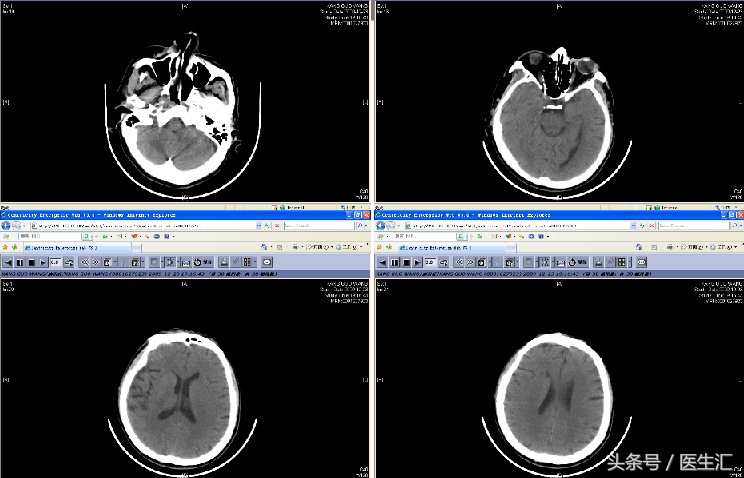

头颅CT